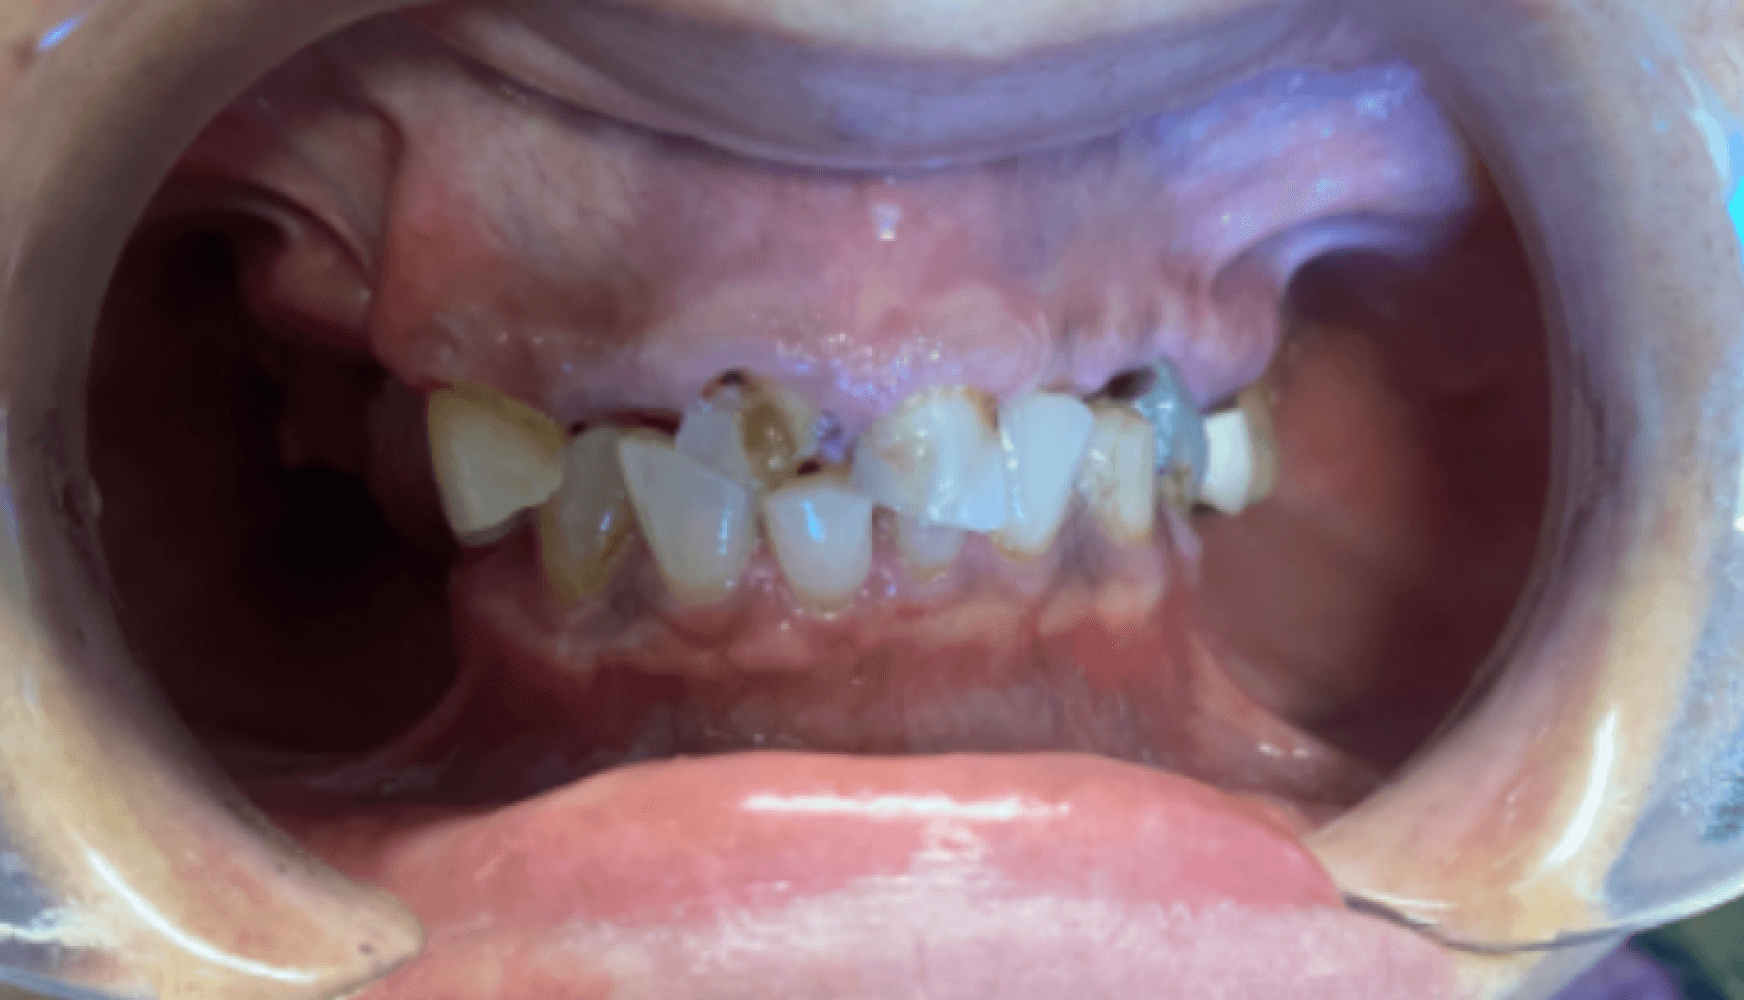

Fig. 1a, 1b, 1c, 1d: The patient’s dentition upon examination reveals significant reduction in VDO, a drastic left-to-right tilt in her smile line, and atrophy of the posterior mandibular ridge.

The patient presented with terminal dentition, multiple compromised and missing teeth, and a significant reduction in vertical dimension of occlusion (VDO) due to years of attrition and bruxism. The patient exhibited a drastic left-to-right tilt in her smile line, with significant atrophy of the posterior mandibular ridge. The right temporomandibular joint (TMJ) displayed a non-reducing disc and deviation to the right upon translation. These anatomical challenges, combined with the patient’s desire for improved function and aesthetics, necessitated a multi-phase treatment plan, beginning with immediate dentures and progressing to implant-supported dentures.